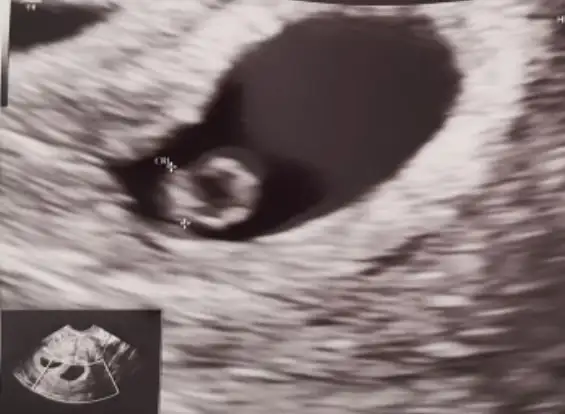

Seninkide erkek canım maşallahBir de bu var daha küçük tabi burda

kuzum tam emin olmamakla söylüyorum erkek gibi

Ay sağol canım çin takvimi de erkek diyorum bakalım artık hayırlısıkuzum tam emin olmamakla söylüyorum erkek gibi

Vajinal ise kız canımYa cok ozendim bizi de tahminler misin :) vajinal bakilmisti. 6+1

Valla ikiside kız gibi canım durma pozisyonları aynı oldugu için ikiz olduguna dikkat etmedim ortadaki ve alttakine baktım aynı görünümce fark edemedim tabiki eglence olsun diye tahminde bulunuyoruz kuzum allah bilir yanlış çıkanda oluyor zatenYa cok ozendim bizi de tahminler misin :) vajinal bakilmisti. 6+1